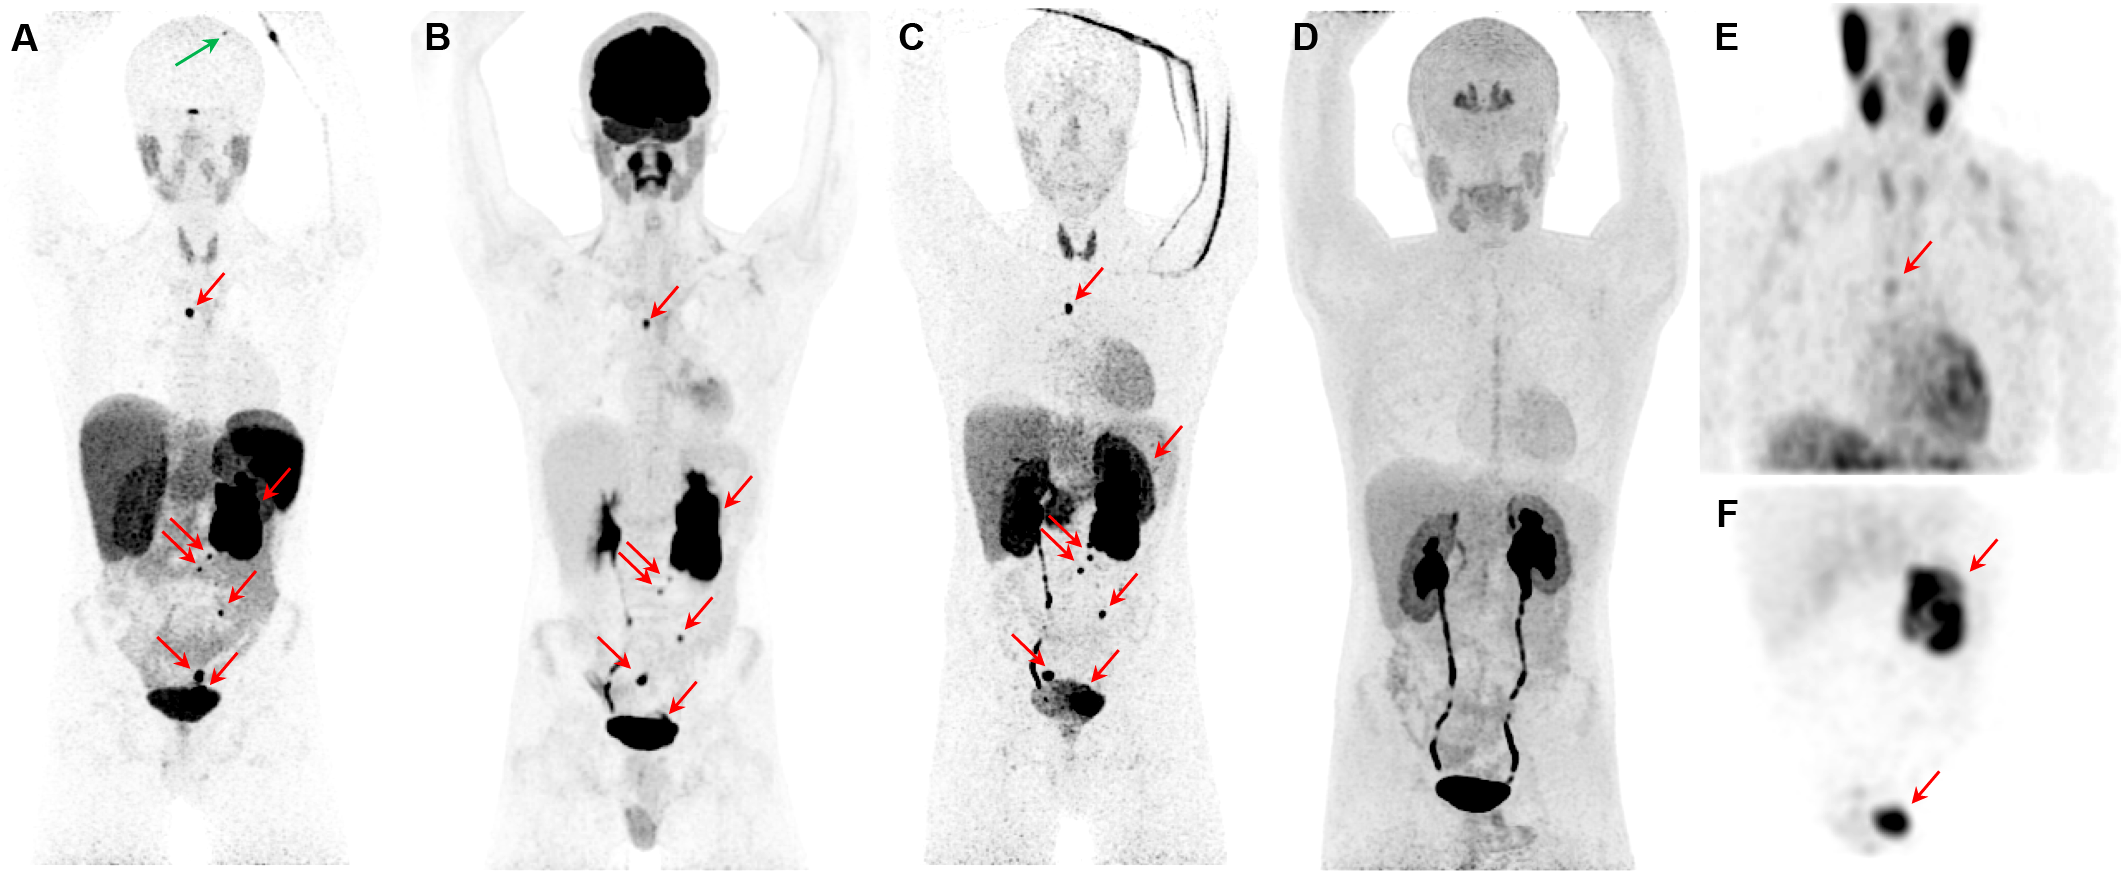

Figure 3

Metastatic pheochromocytoma. The maximum intensity projection images of [68Ga]Ga-DOTATATE PET (A), [18F]FDG PET (B), 18F-fluorodopamine ([18F]FDA) PET (C), 6-[18F]FDOPA PET (D), and [123I]I-mIBG SPECT/CT (E, F) of a 16-year-old boy with metastatic PPGL carrying a germline mutation in SDHB gene demonstrates a 5.7-cm left lesion in the adrenal/periadrenal region abutting the left upper renal pole along with lesions in the abdomen, mesentery, left peri-rectal and precarinal (red arrows) regions, and skull (green arrow). The [68Ga]Ga-DOTATATE PET detects an additional lesion in skull bone (blue arrow); however, 6-[18F]FDOPA failed to detect any lesions.